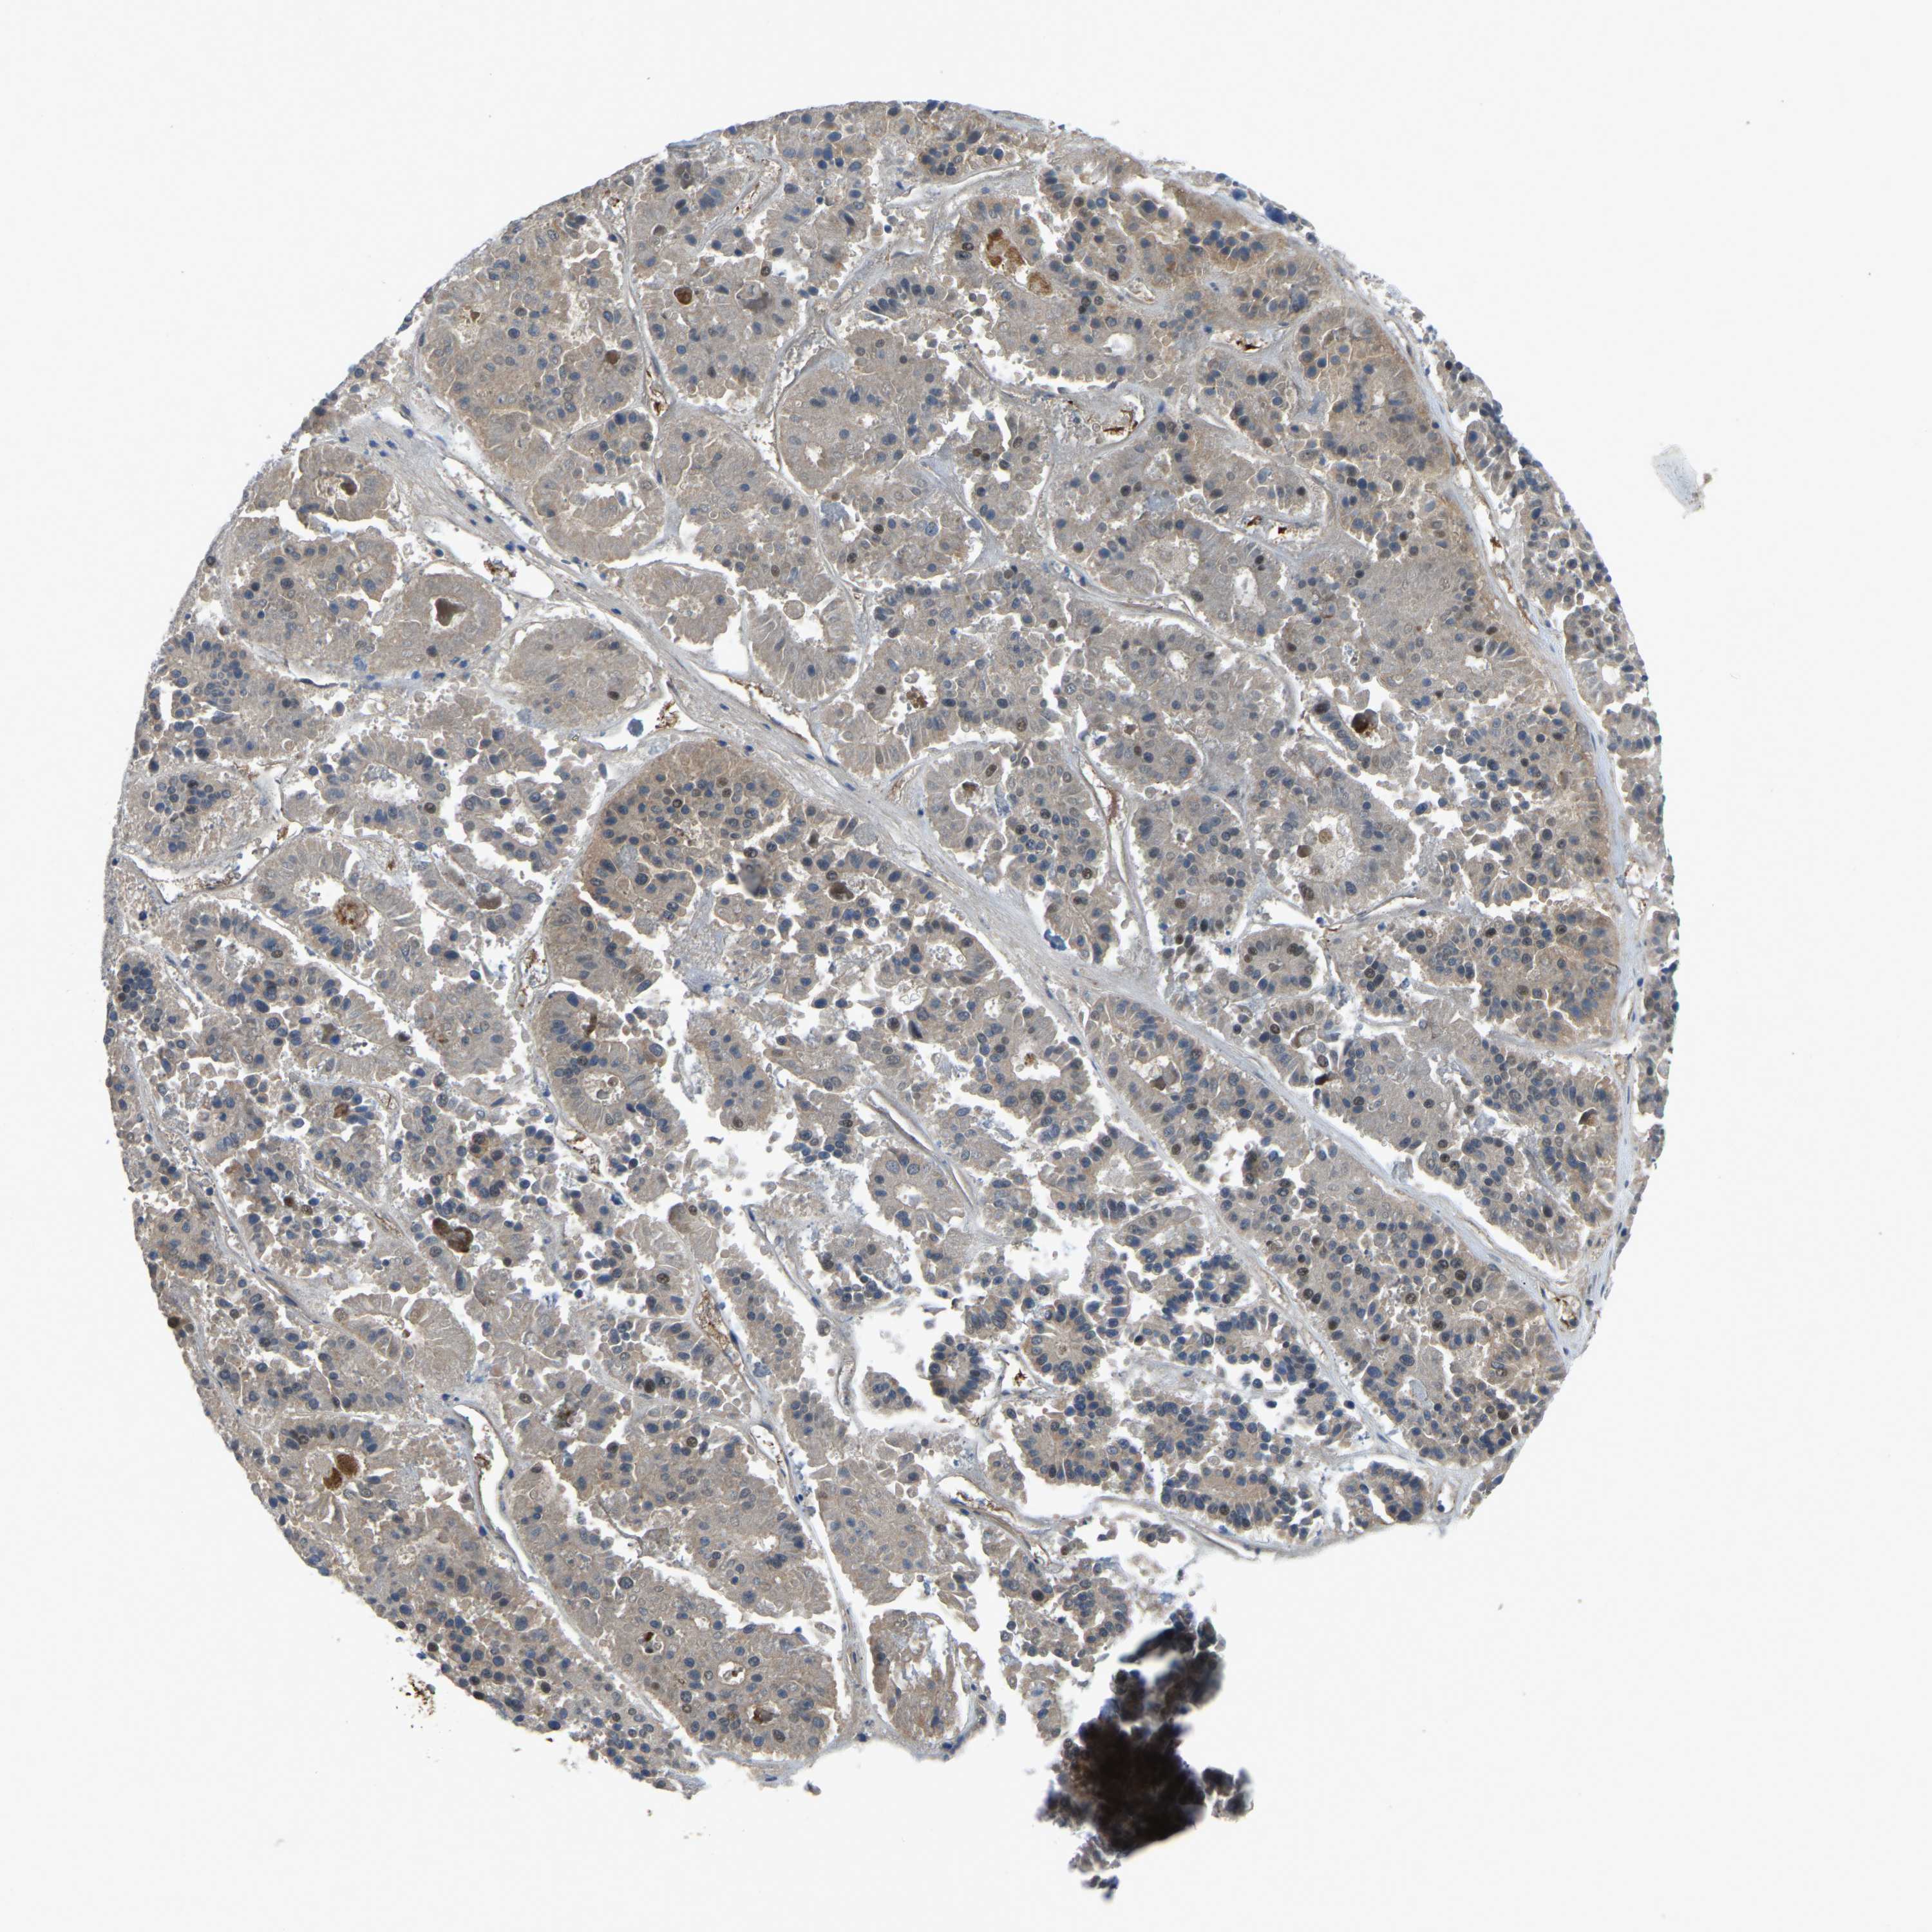

PANCREATIC CANCER - Protein expressioni

A mouse-over function shows sample information and annotation data. Click on an image to view it in a full screen mode. Samples can be filtered based on level of antibody staining by selecting one or several of the following categories: high, medium, low and not detected. The assay and annotation is described here.

Note that samples used for immunohistochemistry by the Human Protein Atlas do not correspond to samples in the TCGA dataset.

Antibody stainingi

Antibody staining in the annotated cell types in the current human tissue is reported as not detected, low, medium, or high, based on conventional immunohistochemistry profiling in selected tissues. This score is based on the combination of the staining intensity and fraction of stained cells.

Each image is clickable and will lead to virtual microscopy that enables deeper exploration of all samples and also displays staining intensity scores, fraction scores and subcellular localization as well as patient and tissue information for each sample.

Antibody HPA018840

Antibody HPA018909

Antibody CAB002684

Staining

High

Medium

Low

Not detected

Intensity

Strong

Moderate

Weak

Negative

Quantity

>75%

75%-25%

<25%

None

Location

Nuclear

Cytoplasmic/membranous

Cytoplasmic/membranous,nuclear

Adenocarcinoma, NOS

Adenocarcinoma, metastatic, NOS